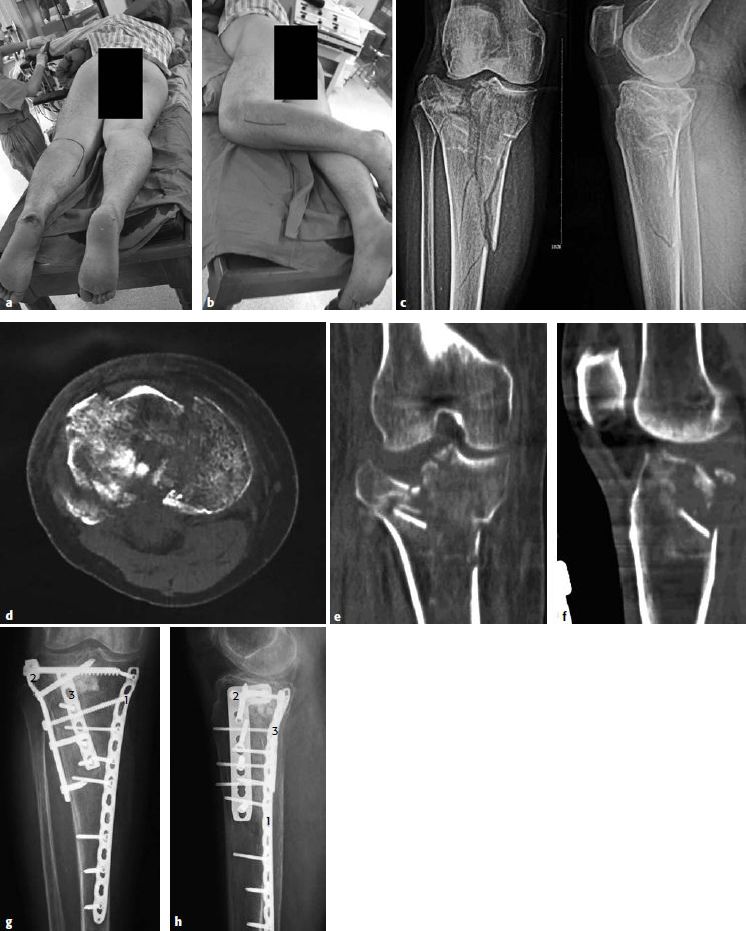

图6.8.1-25 a-h 三柱骨折一名59岁女性机动车车祸时右腿发生了复杂的胫骨平台骨折a-b  漂浮体位下的联合入路;c  术前X线;d  CT轴位片;e  CT冠状位提示内、外侧柱均受累;f  CT矢状位提示后侧柱骨折;g-h  术后X线。钢板1用来支撑内侧柱以防止发生内翻;钢板2用来复位外侧平台和关节;钢板3用来复位和固定胫骨平台的后侧中央区域

累及后侧柱外侧部分的三柱骨折是所有类型胫骨平台骨折中最具有挑战性的类型。可采用「漂浮体位」下的后侧倒L入路联合前外侧入路来处理这种类型的骨折(图6.8.1‑25)。